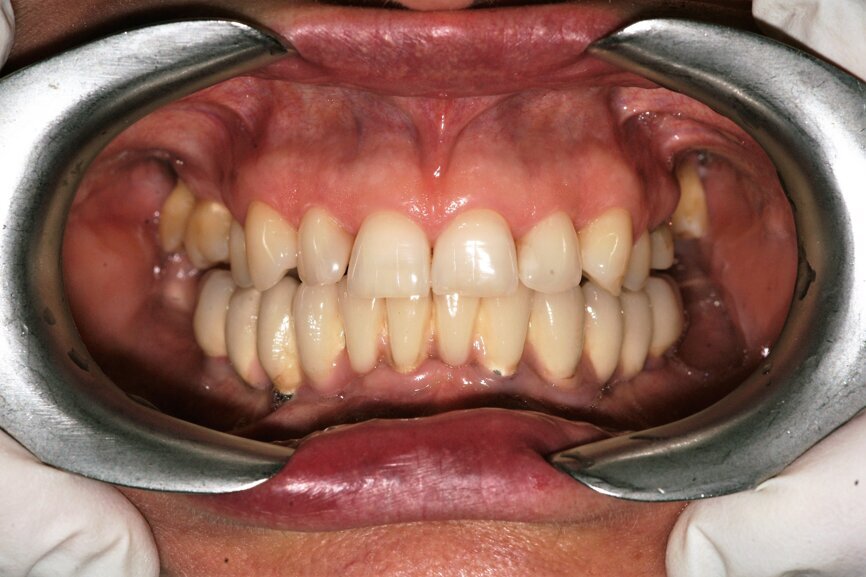

Badaniem wewnątrzustnym stwierdzono kieszenie o głębokości ponad 4 mm, wydzielinę ropną i krwawą, wskaźniki higieny wynosiły odpowiednio: API 25%, SBI 20%, wszystkie zęby w żuchwie wykazywały 3. stopień rozchwiania (Ryc. 1).